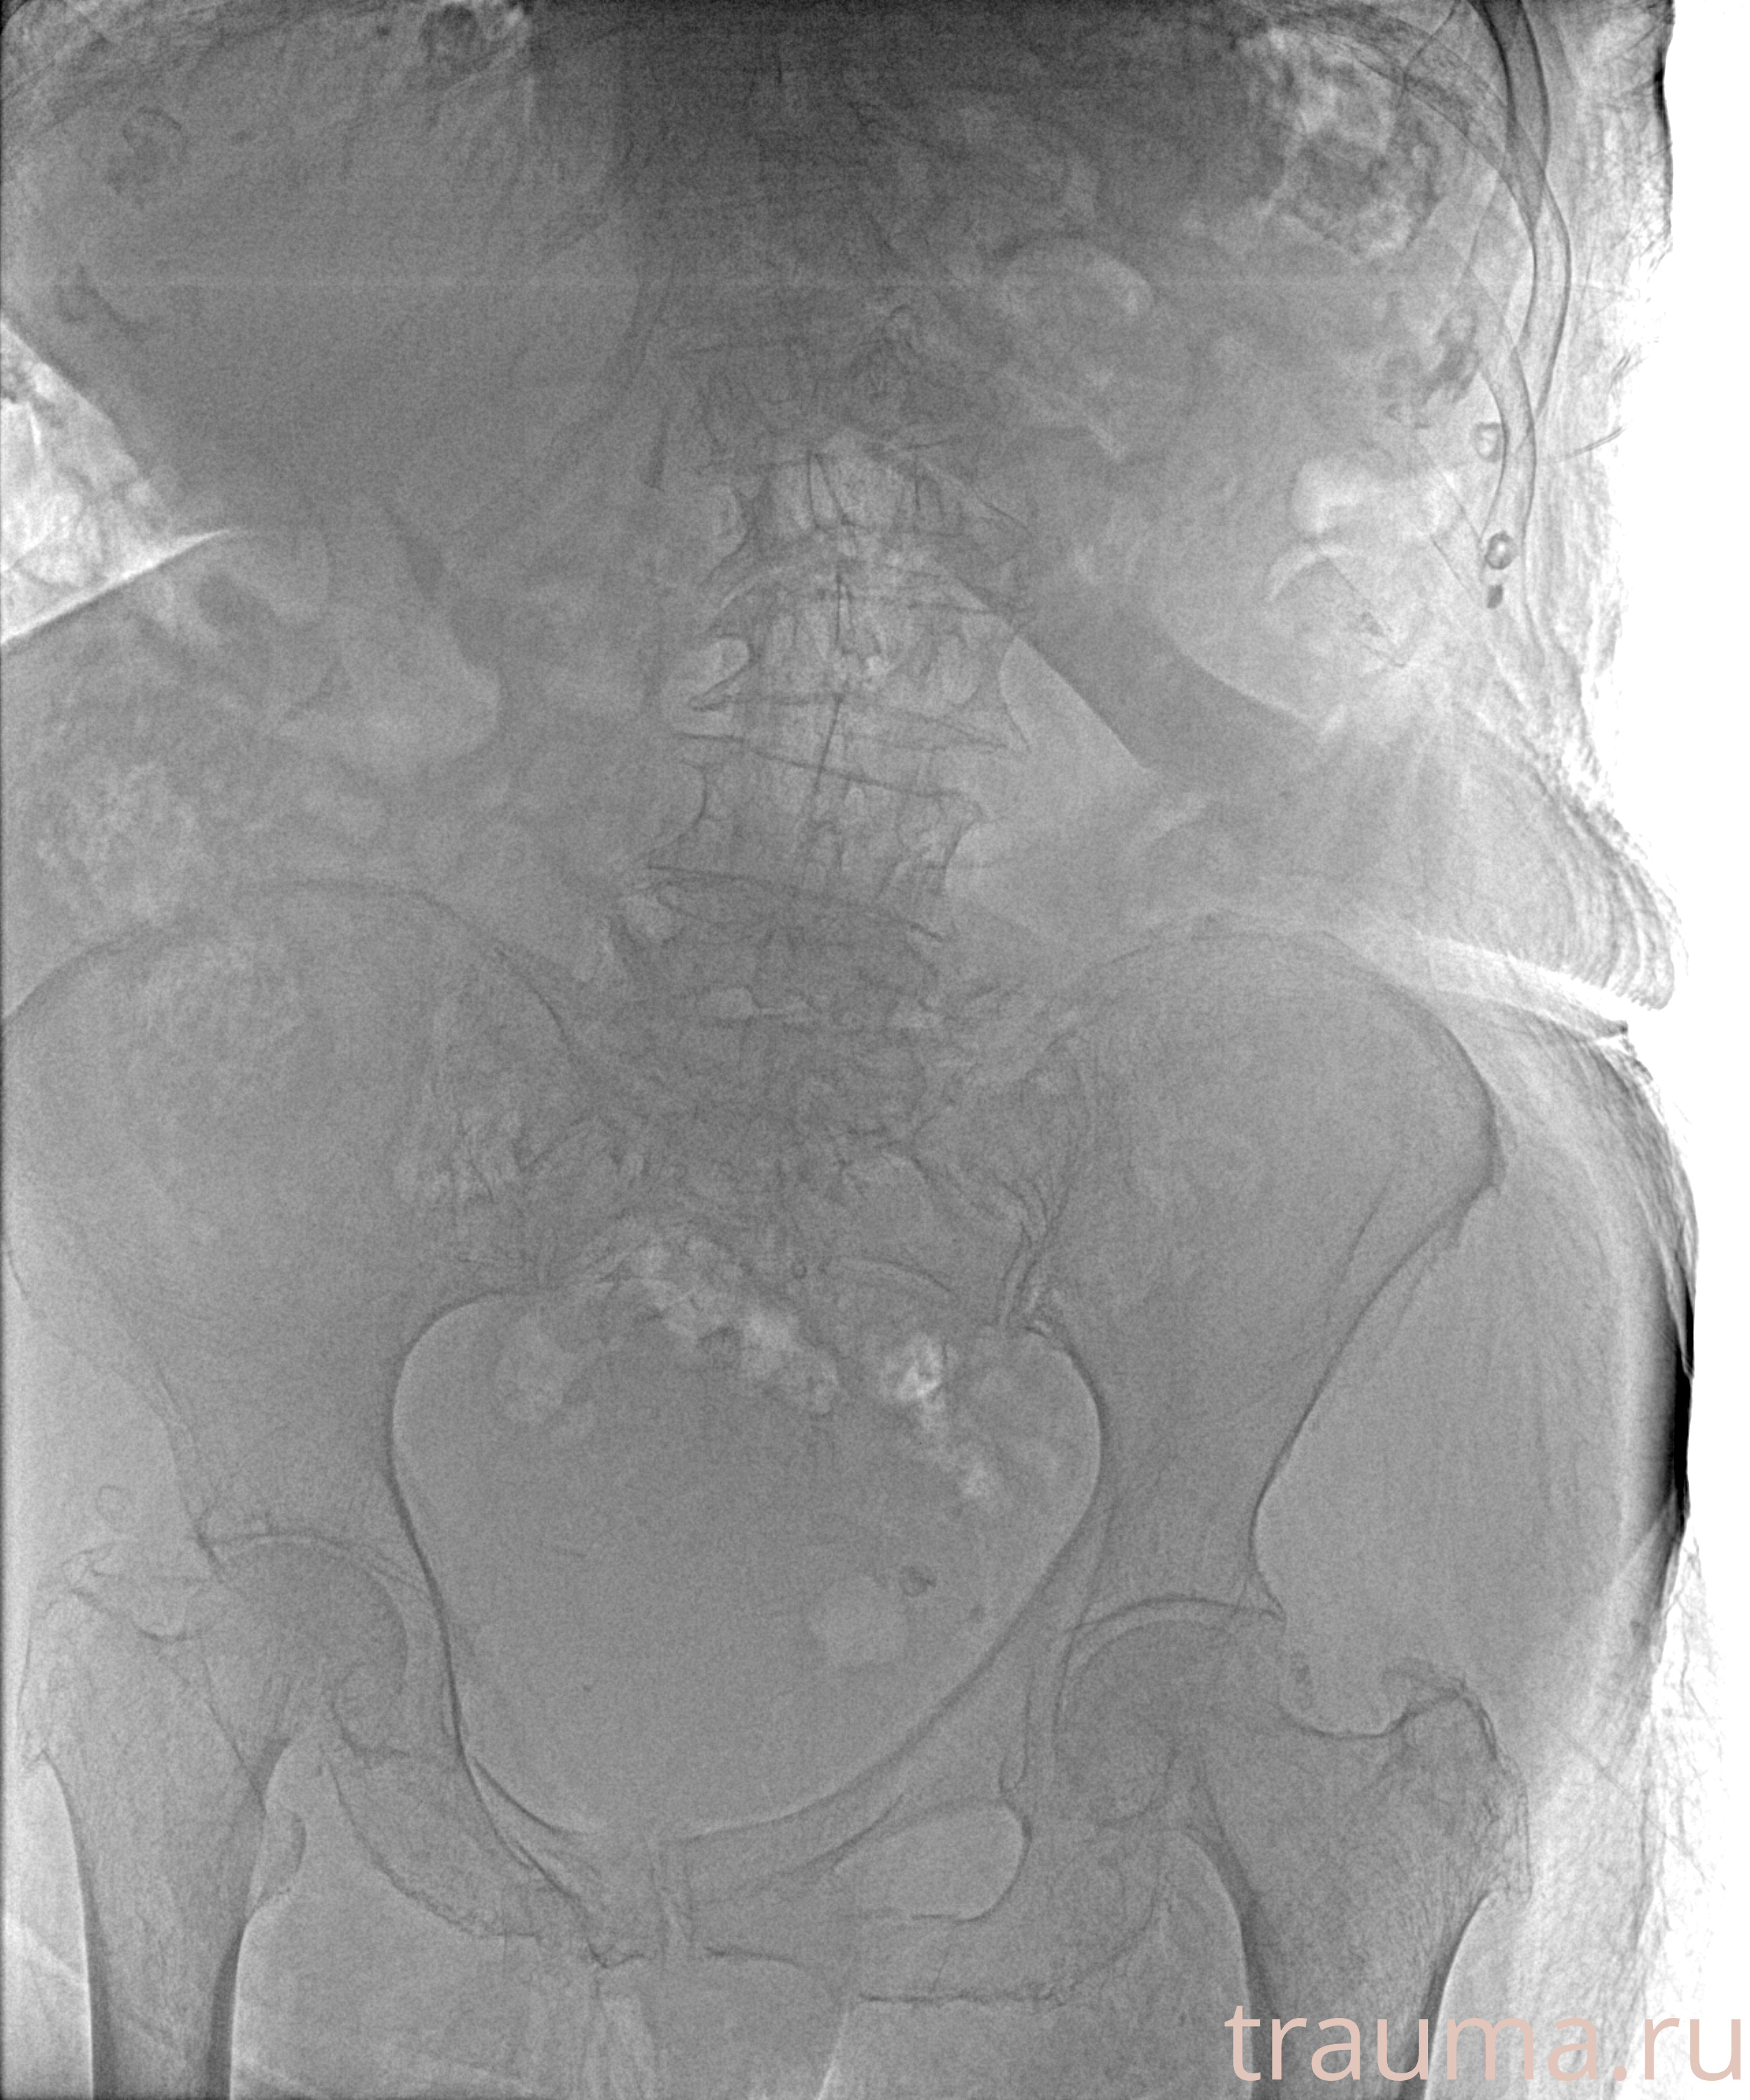

Рентгенограммы

Рентген на дому: по вашему адресу приезжает врач-рентгенолог, травматолог-ортопед с мобильным рентгеновским аппаратом, проводит диагностику травмы или заболевания, делает необходимые рентгенограммы, дает рекомендации по дальнейшему лечению. Получить качественные снимки в домашних условиях возможно благодаря уникальной методике, разработанной МосРентген Центром для института  Склифосовского